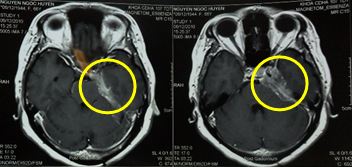

Hình 2: Sau điều trị xạ phẫu 6 tháng: u màng não còn rất nhỏ, giảm kích thước trên 80 %, bệnh nhân thuyên giảm triệu chứng tê mặt, thị lực mắt trái tốt hơn

Hình 3: Sau điều trị 10 tháng: u màng não còn rất nhỏ, bệnh nhân thỉnh thoảng đau nửa mặt trái.